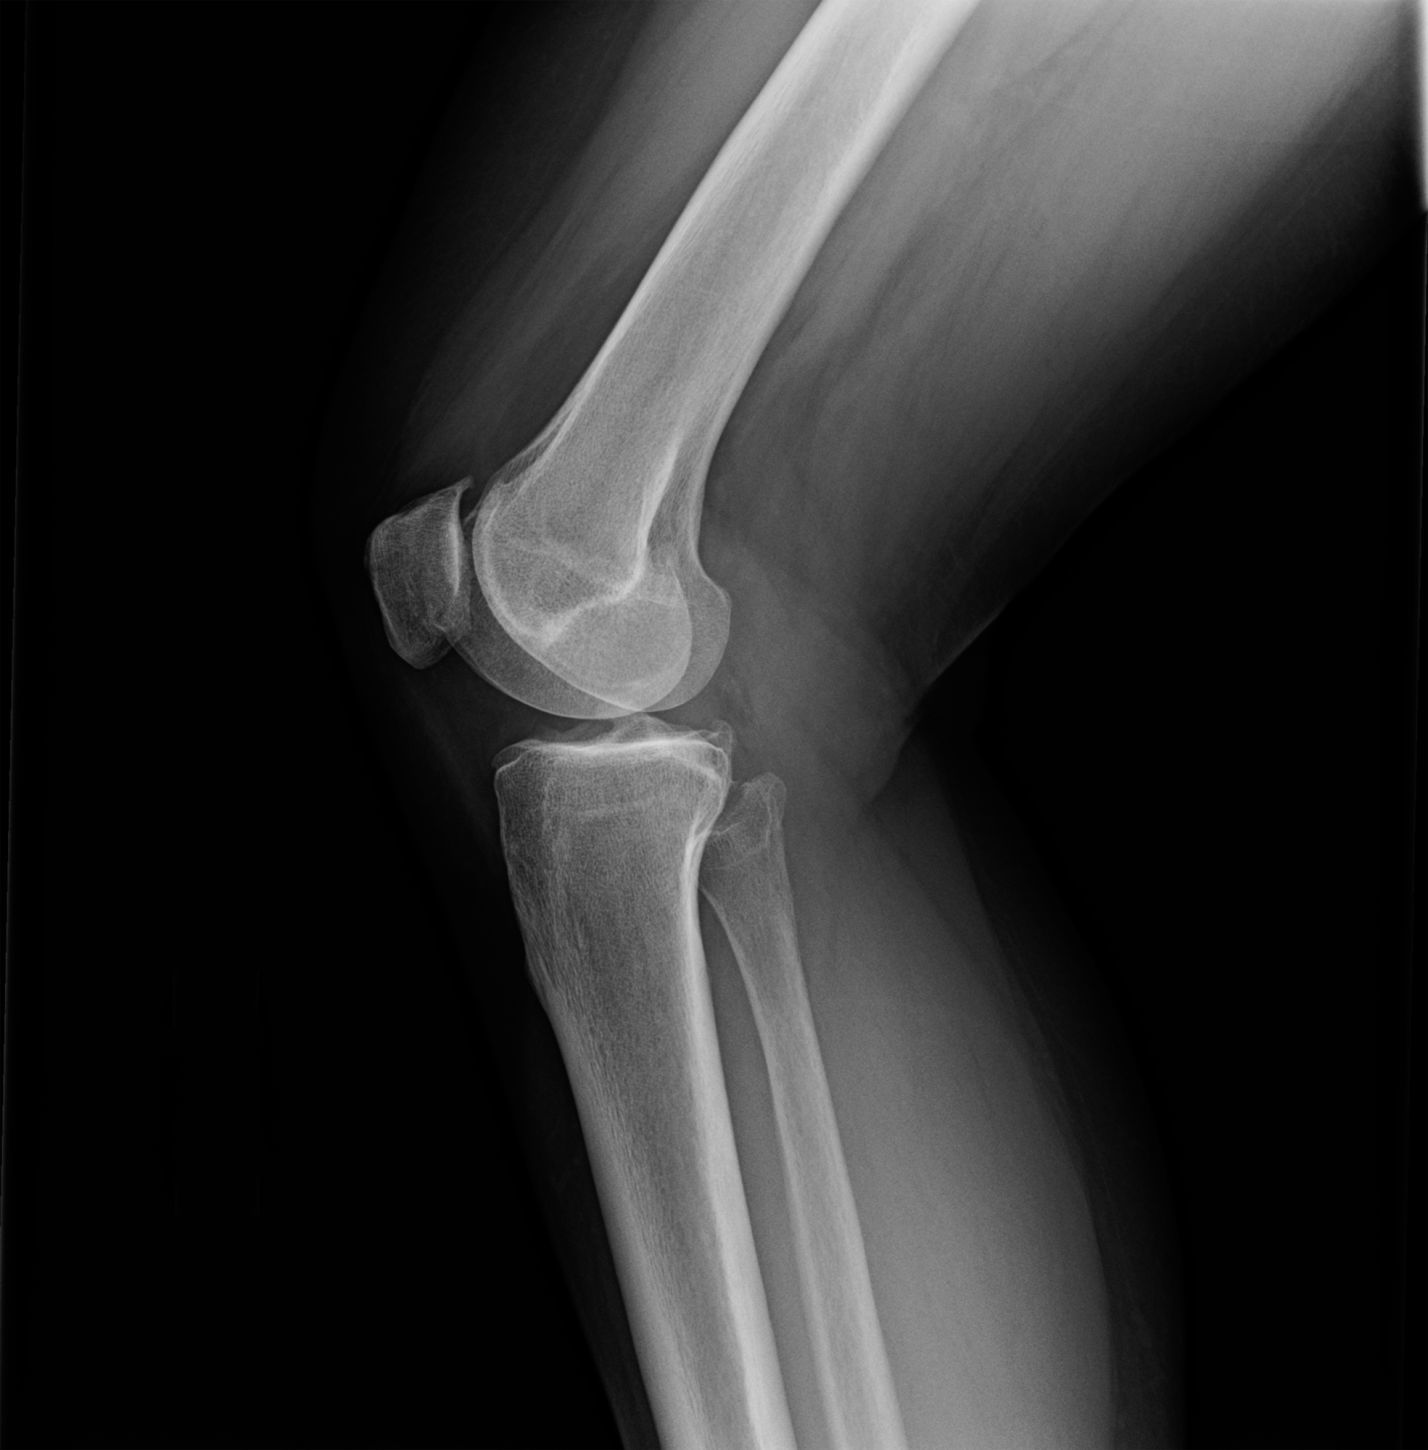

Since bone spurs often don’t cause symptoms, patients usually discover they have them when undergoing an X-ray for another reason. However, when symptoms are present, doctors may use various diagnostic tools:

- X-rays: These can reveal bone spurs and joint damage

- MRI or CT scans: These provide more detailed images of soft tissues and bone structures

Поскольку костные шпоры обычно протекают бессимптомно, пациенты обычно узнают, что они у них есть, только когда они проходят рентген.

Ваш врач, скорее всего, будет использовать рентген для поиска изменений в структуре кости. Можно использовать и другие визуализирующие тесты. К ним относятся тесты МРТ, которые обеспечивают детальное изображение мягких тканей, таких как связки и хрящи, и компьютерная томография, которая может предоставить более подробные изображения костей и других тканей, чем рентген.

Ваш врач также изучит вашу историю болезни, выслушает описание ваших симптомов и проведет медицинский осмотр. Например, если подозрение на костную шпору находится в вашем колене, ваш врач попросит вас пошевелить коленом, пока он прощупывает любые аномалии в суставе.